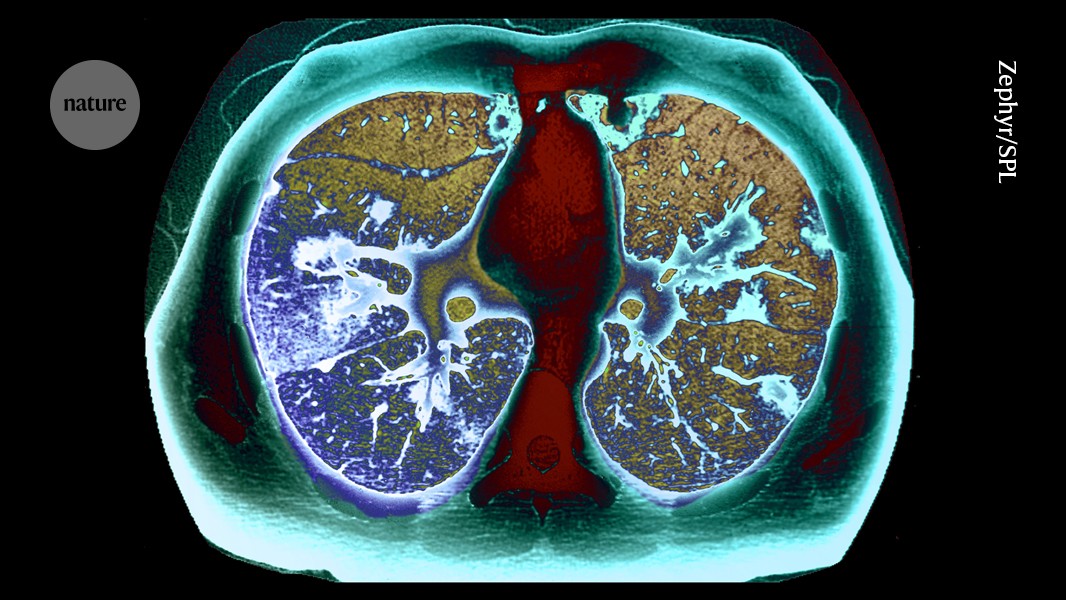

Science Huge lung-cancer screening campaign boosts early diagnosis by admin7 March 28, 2026 0 comments 2 RESEARCH HIGHLIGHT 27 March 2026 A programme that offers scans to smokers between the ages of 55 and 74 detects a large number of early-stage lung tumours. Source link Share 0 FacebookTwitterPinterestEmail previous post James Tolkan, ‘Top Gun’ and ‘Back to the Future’ Actor, Dies at 94 next post US House passes bill funding Homeland Security amid shutdown | Migration You may also like Mystery Deepens: Astrophysicists Say Dark Matter May Not... March 28, 2026 Scientists Create Tiny “Nanolaser” That Could Revolutionize Future... March 28, 2026 Motherhood derails women’s academic careers — these data... March 28, 2026 Mosaic of topless leopard fighter proves female gladiators... March 28, 2026 Your BMI Might Be Wrong: Study Finds Millions... March 28, 2026 Eye drops made from pig semen deliver cancer... March 28, 2026 Researchers detect second Sphinx beneath Pyramids of Giza March 27, 2026 A Simple Blood Test Could Predict Dementia Risk... March 27, 2026 ‘Zombie cells’ resurrected with new genes March 27, 2026 Eleven to 16 storms are expected to hit... March 27, 2026 Leave a Comment Cancel Reply Save my name, email, and website in this browser for the next time I comment.